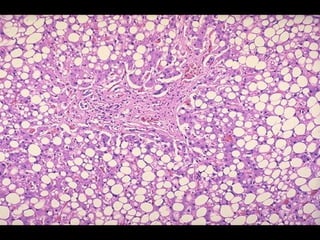

ESTEATOSIS (CAMBIO GRASO) •-Acumulación anómala de triglicéridos dentro de las células parenquimatosas.- •- Se observa con mayor frecuencia en el hígado (principal órgano implicado en el metabolismo graso) pero puede verse también en corazón, músculo y riñón.-

ESTEATOSIS (CAMBIO GRASO) •-Existen diversas causas (toxinas, malnutrición proteica [Kwashiorkor], diabetes mellitus, obesidad, hipoxia) pero la causa más común en adultos es el alcoholismo.- •- El significado del cambio graso depende de la causa y gravedad de la acumulación. La esteatosis es reversible per se.-

INFILTRACIÓN GRASA •- Acumulaciónde lípidos dentro de las células del estroma del tejido conectivo .- •- Se ve, por lo general, en el corazón y en el páncreas; las células adiposas aparecen dentro del estroma del tejido conectivo.- •- Raras veces afecta la función cardiaca o pancreática.-